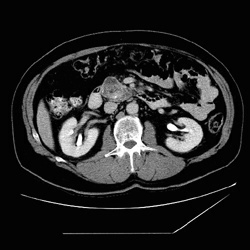

RADIOLOGY: PANCREAS: Case# 102: PANCREATIC ADENOCARCINOMA-DUOD. (S/P DISTAL PANC.). The patient is a 57-year-old white male with duodenal mass. EGD biopsy showed adenocarcinoma. The patient has a history of distal pancreatectomy secondary to pseudocyst formation. There is a 3.4 x 5.0 cm mass within the head of the pancreas. Within this mass there are some cystic areas with calcifications. This mass protrudes into the lumen of the duodenum near the junction of the second and third portions. There are multiple adjacent lymph nodes. There is a 1.2 x 2.2 cm node anterior to the head of the pancreas along the greater curve of the stomach. Also, there is a 1 x 1 cm aortocaval node posterior to the head of the pancreas. There are multiple other smaller lymph nodes anterior and inferior to the pancreas. There has been a distal pancreatectomy (history of pseudocyst in the past). This almost uniformly fatal cancer is the 4th most common malignant tumor accounting for 5% of cancer deaths in the United States. Symptoms are usually nonspecific and insidious such that the cancer is advanced by the time of diagnosis. Most cancers occur in the head of the pancreas and are usually adenocarcinomas arising from ductal cells. The sensitivity of CT scan in diagnosing pancreatic carcinoma is approximately 95% whereas that of ultrasound is less than 80% for cancer of the head and 40% for the tail. The primary finding on CT is a focal mass;however, if no mass is present, other findings may suggest neoplasm. First, the pancreas may become more heterogeneous in density with age. Thus, a focal region of homogeneous soft tissue density might raise suspicion of a carcinoma. The presence of both a dilated common bile duct and a dilated main pancreatic duct in the absence of calculus suggests ampullary or pancreatic head neoplasm, but this may also be seen in benign disease. The finding of a dilated main pancreatic duct in the body or tail but not in the head or neck suggests neoplasm, and finally, the finding of rounded convex borders of both anterior and posterior surfaces of the uncinate process raises suspicion for carcinoma. Ten to fifteen percent of patients will have potentially resectable tumors, and they may be distinguished by CT findings. Signs of potential resectability include an isolated pancreatic mass with or without dilatation of the bile and pancreatic ducts and combined bile-pancreatic duct dilatation without an identifiable pancreatic mass. Extension of the tumor beyond the margins of the pancreas, involvement of adjacent organs or the SMA, liver metastases, ascites, and regional adenopathy are signs of unresectability. Unfortunately, most of those who undergo resection eventually die of pancreatic cancer.